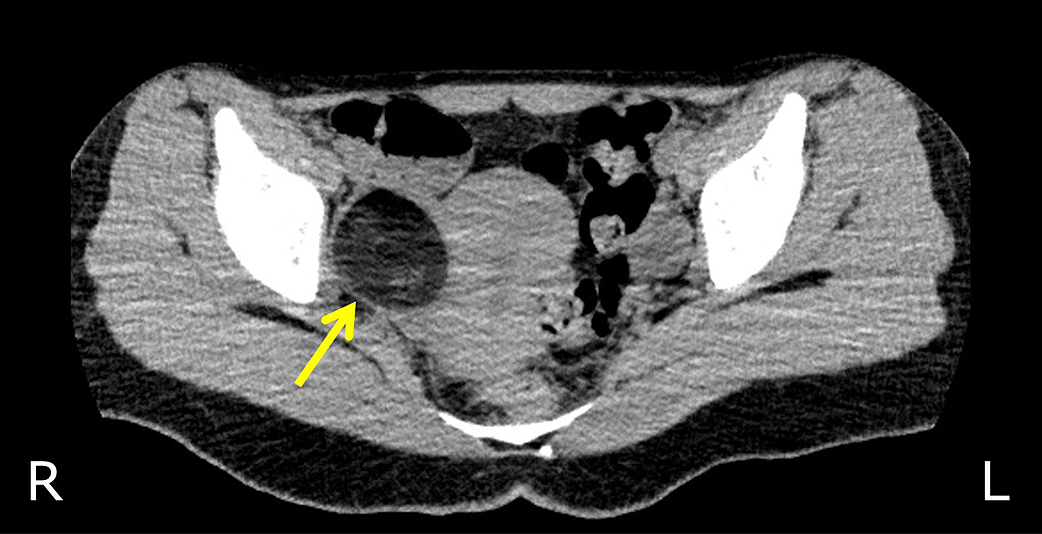

卵巣成熟奇形腫を合併した抗NMDA受容体抗体陰性自己免疫性脳炎に対して早期の腫瘍摘出術が奏効した18歳女性例

A case of autoantibody-negative autoimmune encephalitis associated with mature ovarian teratoma, successfully treated with early ovariectomy

髙橋 健祐, 佐々木 拓也, 川﨑 怜子, 前田 れな, 角田 幸雄, 今福 一郎

Kensuke Takahashi, Takuya Sasaki, Reiko Kawasaki, Rena Maeda, Yukio Kakuta, Ichiro Imafuku